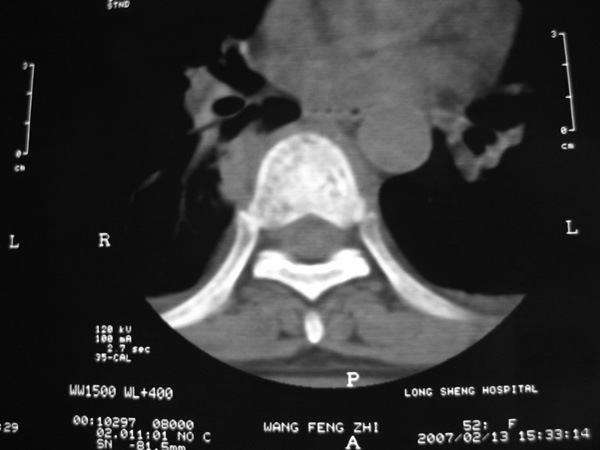

女,45岁,胸背部疼痛2个月。t6、7胸椎病变。

椎旁肿胀的软组织内可见气泡影,对脊柱的化脓性和结核性的鉴别有帮助吗?

胸椎结核与脊柱椎体化脓性脊柱炎,从影像特点很难鉴别,本例具有二者的共性特点,建议结合临床鉴别以下,我考虑:1 化脓性脊柱炎.2 胸椎结核.原因:1 椎旁脓肿内含气泡.2 椎体溶骨性破坏,但未见死骨.

胸椎体骨质破坏伴死骨形成,椎周环状软组织肿胀,范围较长,考虑胸椎结核伴冷脓肿形成。鉴别;1转移性肿瘤;椎弓根骨质破坏多见,软组织肿块局限。椎间隙尚存。有原发肿瘤病史。2,淋巴瘤;骨质破坏 然骨皮质轮廓线尚存,当椎管骨示环状软组织影时有一定特异性。病变较局限。建议mri增强,观察冷脓肿与软组织肿块很有帮助。

胸椎结核与脊柱椎体化脓性脊柱炎,从影像特点很难鉴别,本例具有二者的共性特点,建议结合临床鉴别以下,我考虑:1 胸椎结核.2 化脓性脊柱炎.原因: 椎体溶骨性破坏,但未见死骨.我认为大家说的气泡是假象。